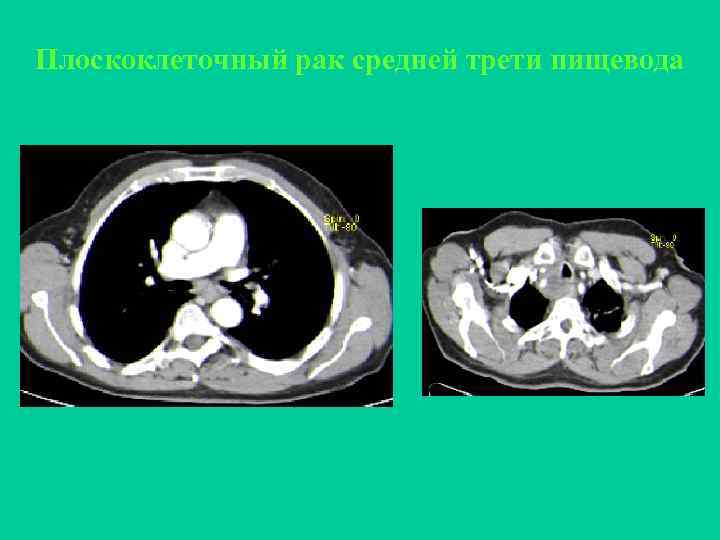

Плоскоклеточный рак средней трети пищевода